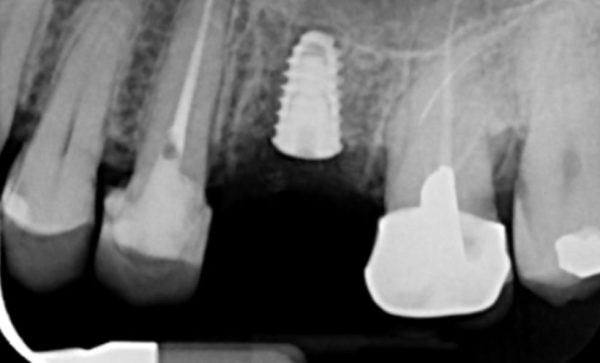

Case 47